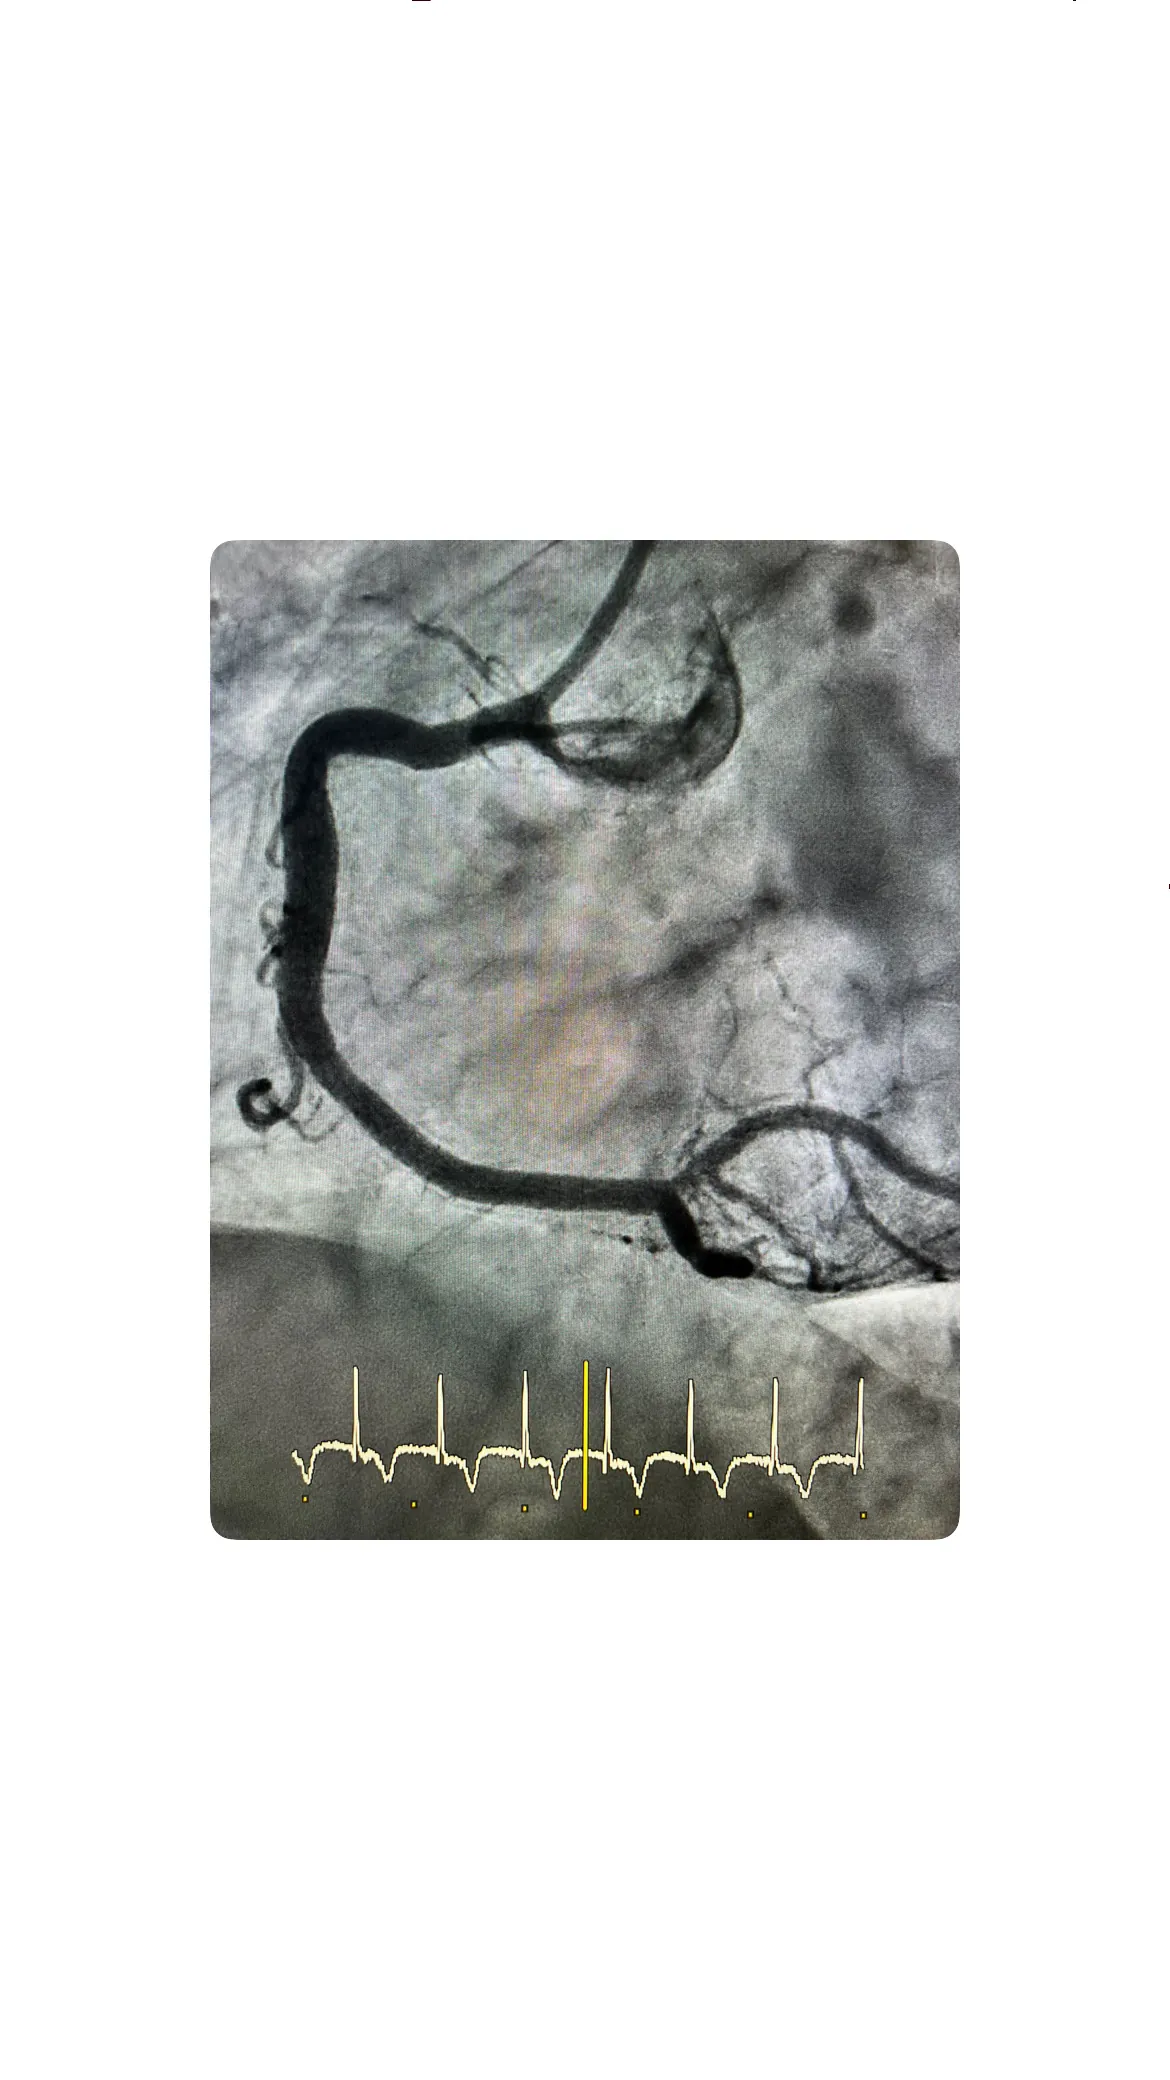

Tras identificar la oclusión, se procede a pasar una guía a través de la lesión, maniobra que requiere precisión para atravesar el segmento trombótico sin provocar disecciones ni complicaciones adicionales. Una vez la guía está bien posicionada, se realiza aspiración del trombo, técnica que en este caso resulta efectiva, logrando retirar material trombótico y mejorar parcialmente el flujo. Posteriormente se lleva a cabo la predilatación con balones, inflándolos en el punto de la lesión para abrir la arteria y preparar el lecho vascular, de modo que el stent pueda expandirse correctamente y asegurar una revascularización óptima.

Implantación del stent y resultado del procedimiento

Una vez conseguida la recuperación inicial del flujo y tras preparar adecuadamente la lesión con la predilatación, se procede a la implantación del stent en la arteria afectada. El stent se posiciona cuidadosamente en el segmento previamente ocluido y se expande con un balón, fijándose a la pared arterial para mantener la luz abierta de forma estable. En este caso, el resultado angiográfico final es satisfactorio, con un flujo coronario adecuado y sin complicaciones inmediatas, lo que consolida el éxito del procedimiento.

La paciente se mantiene estable durante toda la intervención, sin arritmias graves ni deterioro hemodinámico, lo que refuerza la idea de un caso real de SCACEST Killip I inferior manejado de forma rápida y eficaz. El hecho de que el cateterismo haya sido “quilipuno”, es decir, no complicado, no resta importancia a la gravedad potencial del cuadro, pero sí pone de relieve el valor de una actuación coordinada y precoz. Con la arteria abierta y el stent correctamente implantado, el foco pasa a la fase de tratamiento farmacológico y a la educación de la paciente para evitar nuevos eventos.